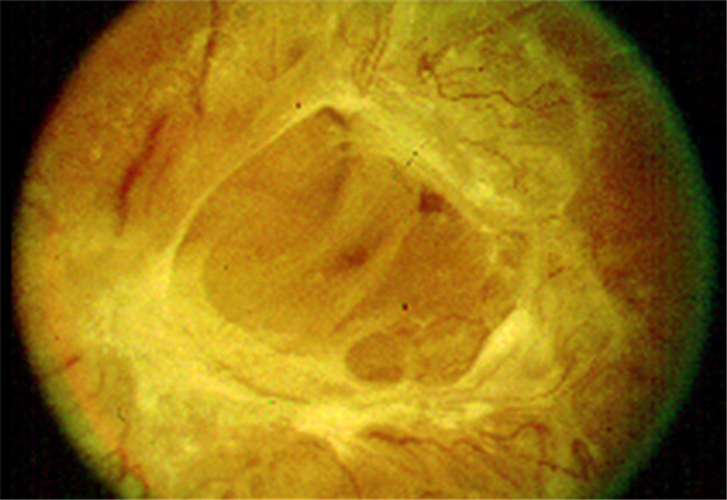

早產兒視網膜脫落

早產兒牽拉性視網膜脫落